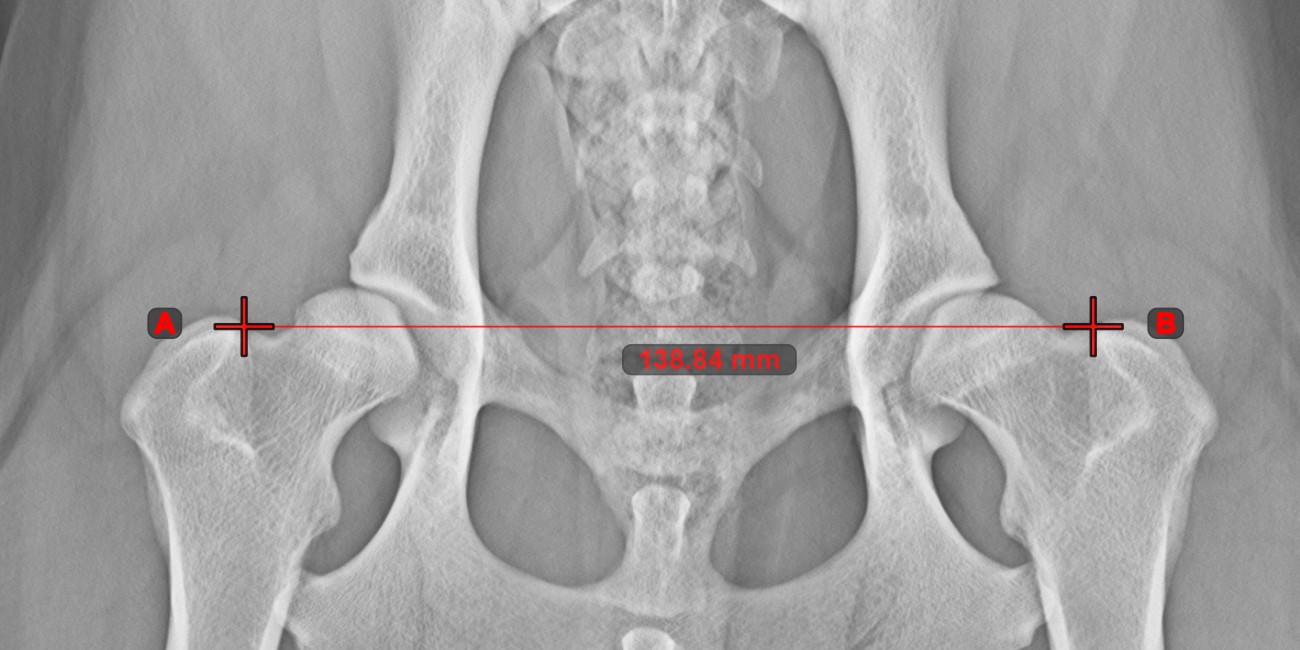

Vonal létrehozása¶

Válassza ki a Vonal létrehozása eszközt, és rendelje hozzá az egyik elérhető egérgombhoz. Helyezze el a kezdő- és végpontot a jelenetben, vagy válassza ki őket a már meglévő pontok közül a képen. A két pont közötti távolság automatikusan kiszámításra kerül az alapértelmezett kalibrációs adatok, vagy a hosszkalibráció mérés által újrakalibrált adatok alapján.

Módosítsa a kezdő- és végpontot az Elem kiválasztása/mozgatása eszközzel. A két pont közötti távolság automatikusan újraszámításra kerül.